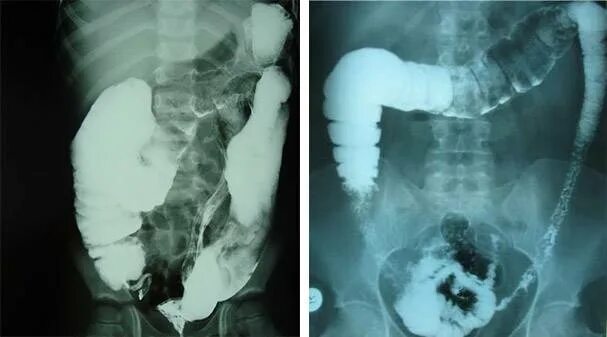

Долихосигма кишечника у ребенка